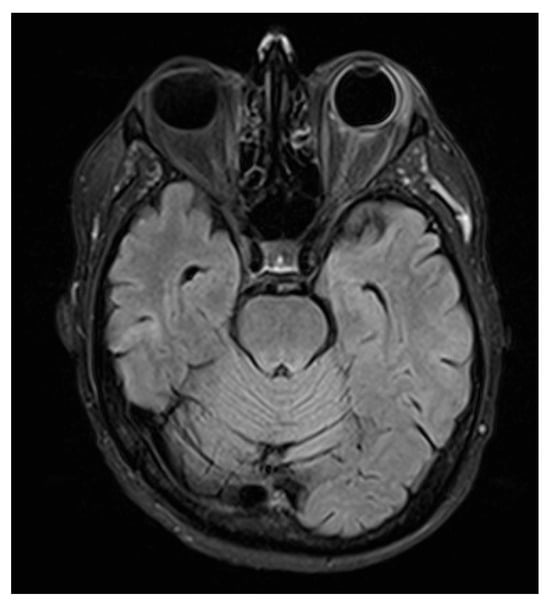

MRI of the brain and orbits was obtained. Neuroimaging demonstrated minute, focal hypointense lesions in both supratentorial and infratentorial regions, compatible with microbleeds, without signal abnormalities suggestive of CNS leukemic localization.

Orbital T2-FLAIR MRI sequences showed mild edema and hyperintensity of the retroorbital and periorbital fat, the lacrimal gland, the posterior sclera, and the optic nerve sheath (Figure 2). B-scan ultrasonography showed fibrotic consolidations and organized vitreous hemorrhage, along with marked choroidal thickening displaying medium–low reflectivity and elevation of the retinal contour, suggestive of infiltrative material (Figure 3). The associated optic disc distortion and perineural sheath edema, together with MRI findings, supported the diagnosis of multifocal leukemic infiltration with adnexal and retrobulbar extension, rather than hemorrhagic changes.

Figure 2. Orbital MRI (T2-FLAIR) showing hyperintensity of the retro- and periorbital fat, posterior sclera, and optic nerve sheath, consistent with leukemic infiltration extending to adnexal and retrobulbar tissues.